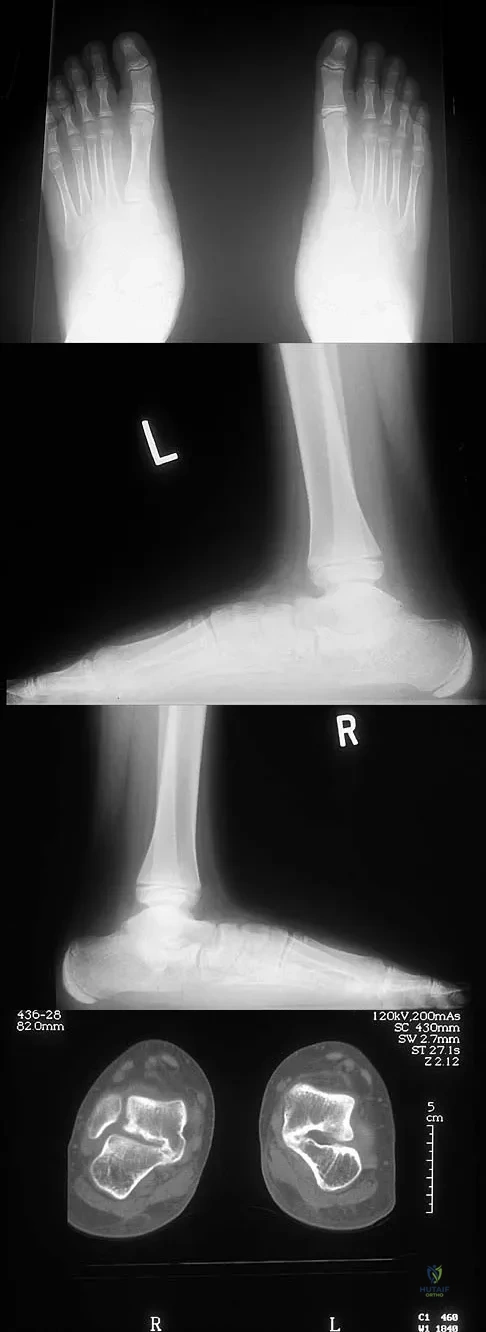

Question 23High Yield

A 12-year-old boy has had progressive pain and flatfeet for the past year. Pain is increased with weight-bearing activities. Examination reveals that subtalar motion is absent. On standing, the patient has obvious hindfoot valgus and loss of the normal arch bilaterally. Plain radiographs are shown in Figures 43a through 43c, and a CT scan is shown in Figure 43d. What is the most likely diagnosis?

Explanation

Question 12 High Yield

What patient factor is predictive of better outcomes for surgical management of a displaced calcaneal fracture compared to nonsurgical management?

Detailed Explanation